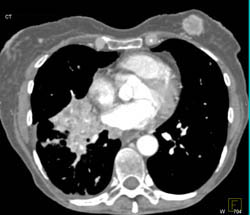

Vascular Mapping for Gluteal Flap Surgery